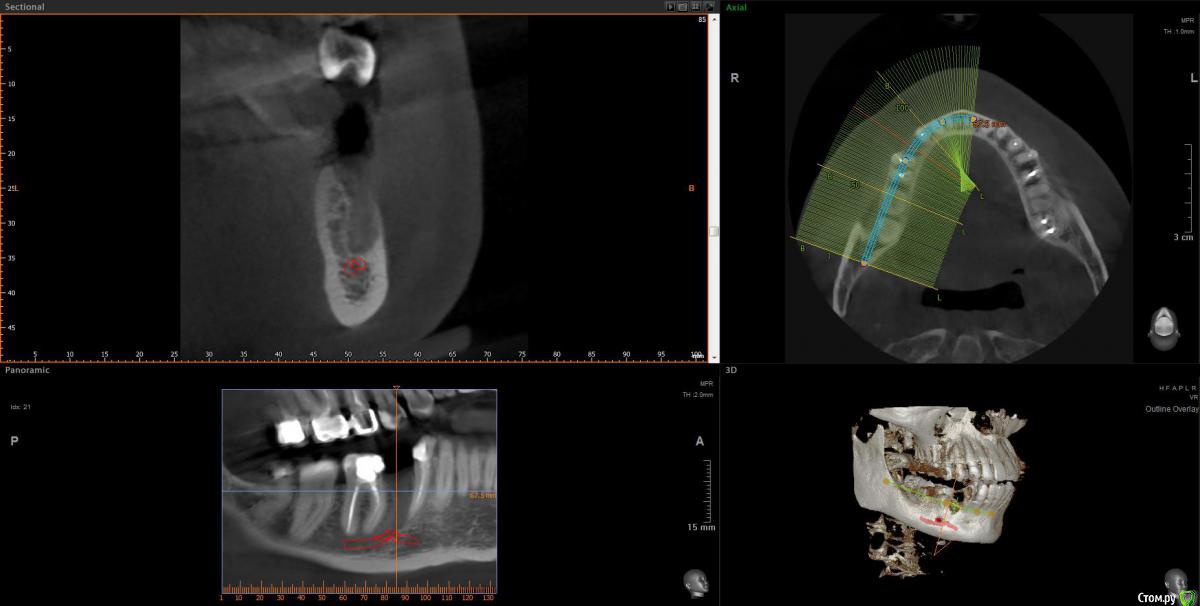

Cleo15 Опубликовано 26 мая, 2020 Поделиться Опубликовано 26 мая, 2020 Добрый день!После удаления нижней пятерки имплантолог на консультации сказал, что корень соседней четверки растет так, что у нас 2 варианта имплантации: либо ставить длинный под наклоном, либо рискнуть установить короткий (10 мм.) вертикально.При этом конструкция под наклоном не столь надежна, как вертикальная вследствие предстоящих проблем с абатментом, а при вертикальной установке существует риск повреждения корня четверки (который я должна взять на себя, следует заметить) плюс долговечность имплантата вследствие его малости также под вопросом.Подскажите, пожалуйста, какой метод предпочтительнее выбрать в такой ситуации? Ссылка на комментарий

Irouil Опубликовано 26 мая, 2020 Поделиться Опубликовано 26 мая, 2020 (изменено) 10 мм - это не короткий имплантат, нужно смотреть КТ, но по этому снимку никаких явных проблем с установкой имплантата я не вижу Зуб давно удалён? Изменено 26 мая, 2020 пользователем Irouil 1 Ссылка на комментарий

Cleo15 Опубликовано 26 мая, 2020 Автор Поделиться Опубликовано 26 мая, 2020 Удален 5 месяцев назад.КТ https://my-files.su/2kio3d Ссылка на комментарий

krokomot Опубликовано 26 мая, 2020 Поделиться Опубликовано 26 мая, 2020 можно и 8мм поставить это не принципиально Ссылка на комментарий

stommm Опубликовано 27 мая, 2020 Поделиться Опубликовано 27 мая, 2020 10мм имплант в правильной ортопедической позиции предпочтительнее 14 мм импланта в неправильной. И 10 это не короткий. И 8 мм нормальный размер. Короткий это 4 мм длина. Ссылка на комментарий

Bier Опубликовано 28 мая, 2020 Поделиться Опубликовано 28 мая, 2020 таки правильно тут ставить с небольшим наклоном. Длина не имеет значения. Ссылка на комментарий